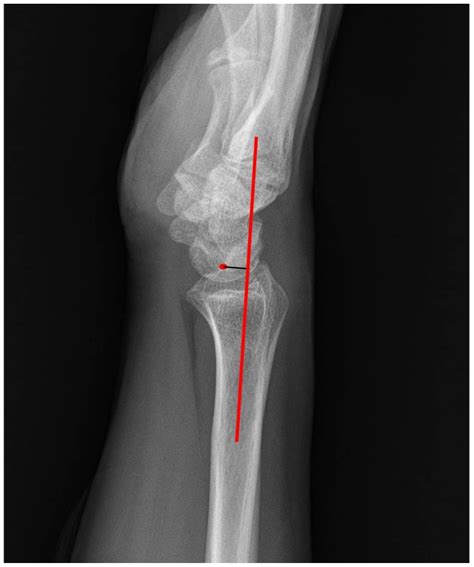

A wrist X-ray is a type of imaging test that uses low doses of radiation to produce images of the bones and joints in the wrist. This procedure is typically performed to diagnose fractures, dislocations, arthritis, and other conditions that affect the wrist. The X-ray images provide detailed views of the bones, allowing healthcare providers to assess their structure and alignment.

While a normal wrist X-ray indicates no significant issues, there are several common findings that healthcare providers look for when interpreting the results. These include:

• Fractures: Breaks in the bones, which can range from small cracks to complete breaks.

• Dislocations: Misalignment of the bones in the wrist joint.

• Arthritis: Degenerative changes in the joints, such as bone spurs or narrowing of the joint space.

• Bone density: Assessment of bone health, which can indicate conditions like osteoporosis.